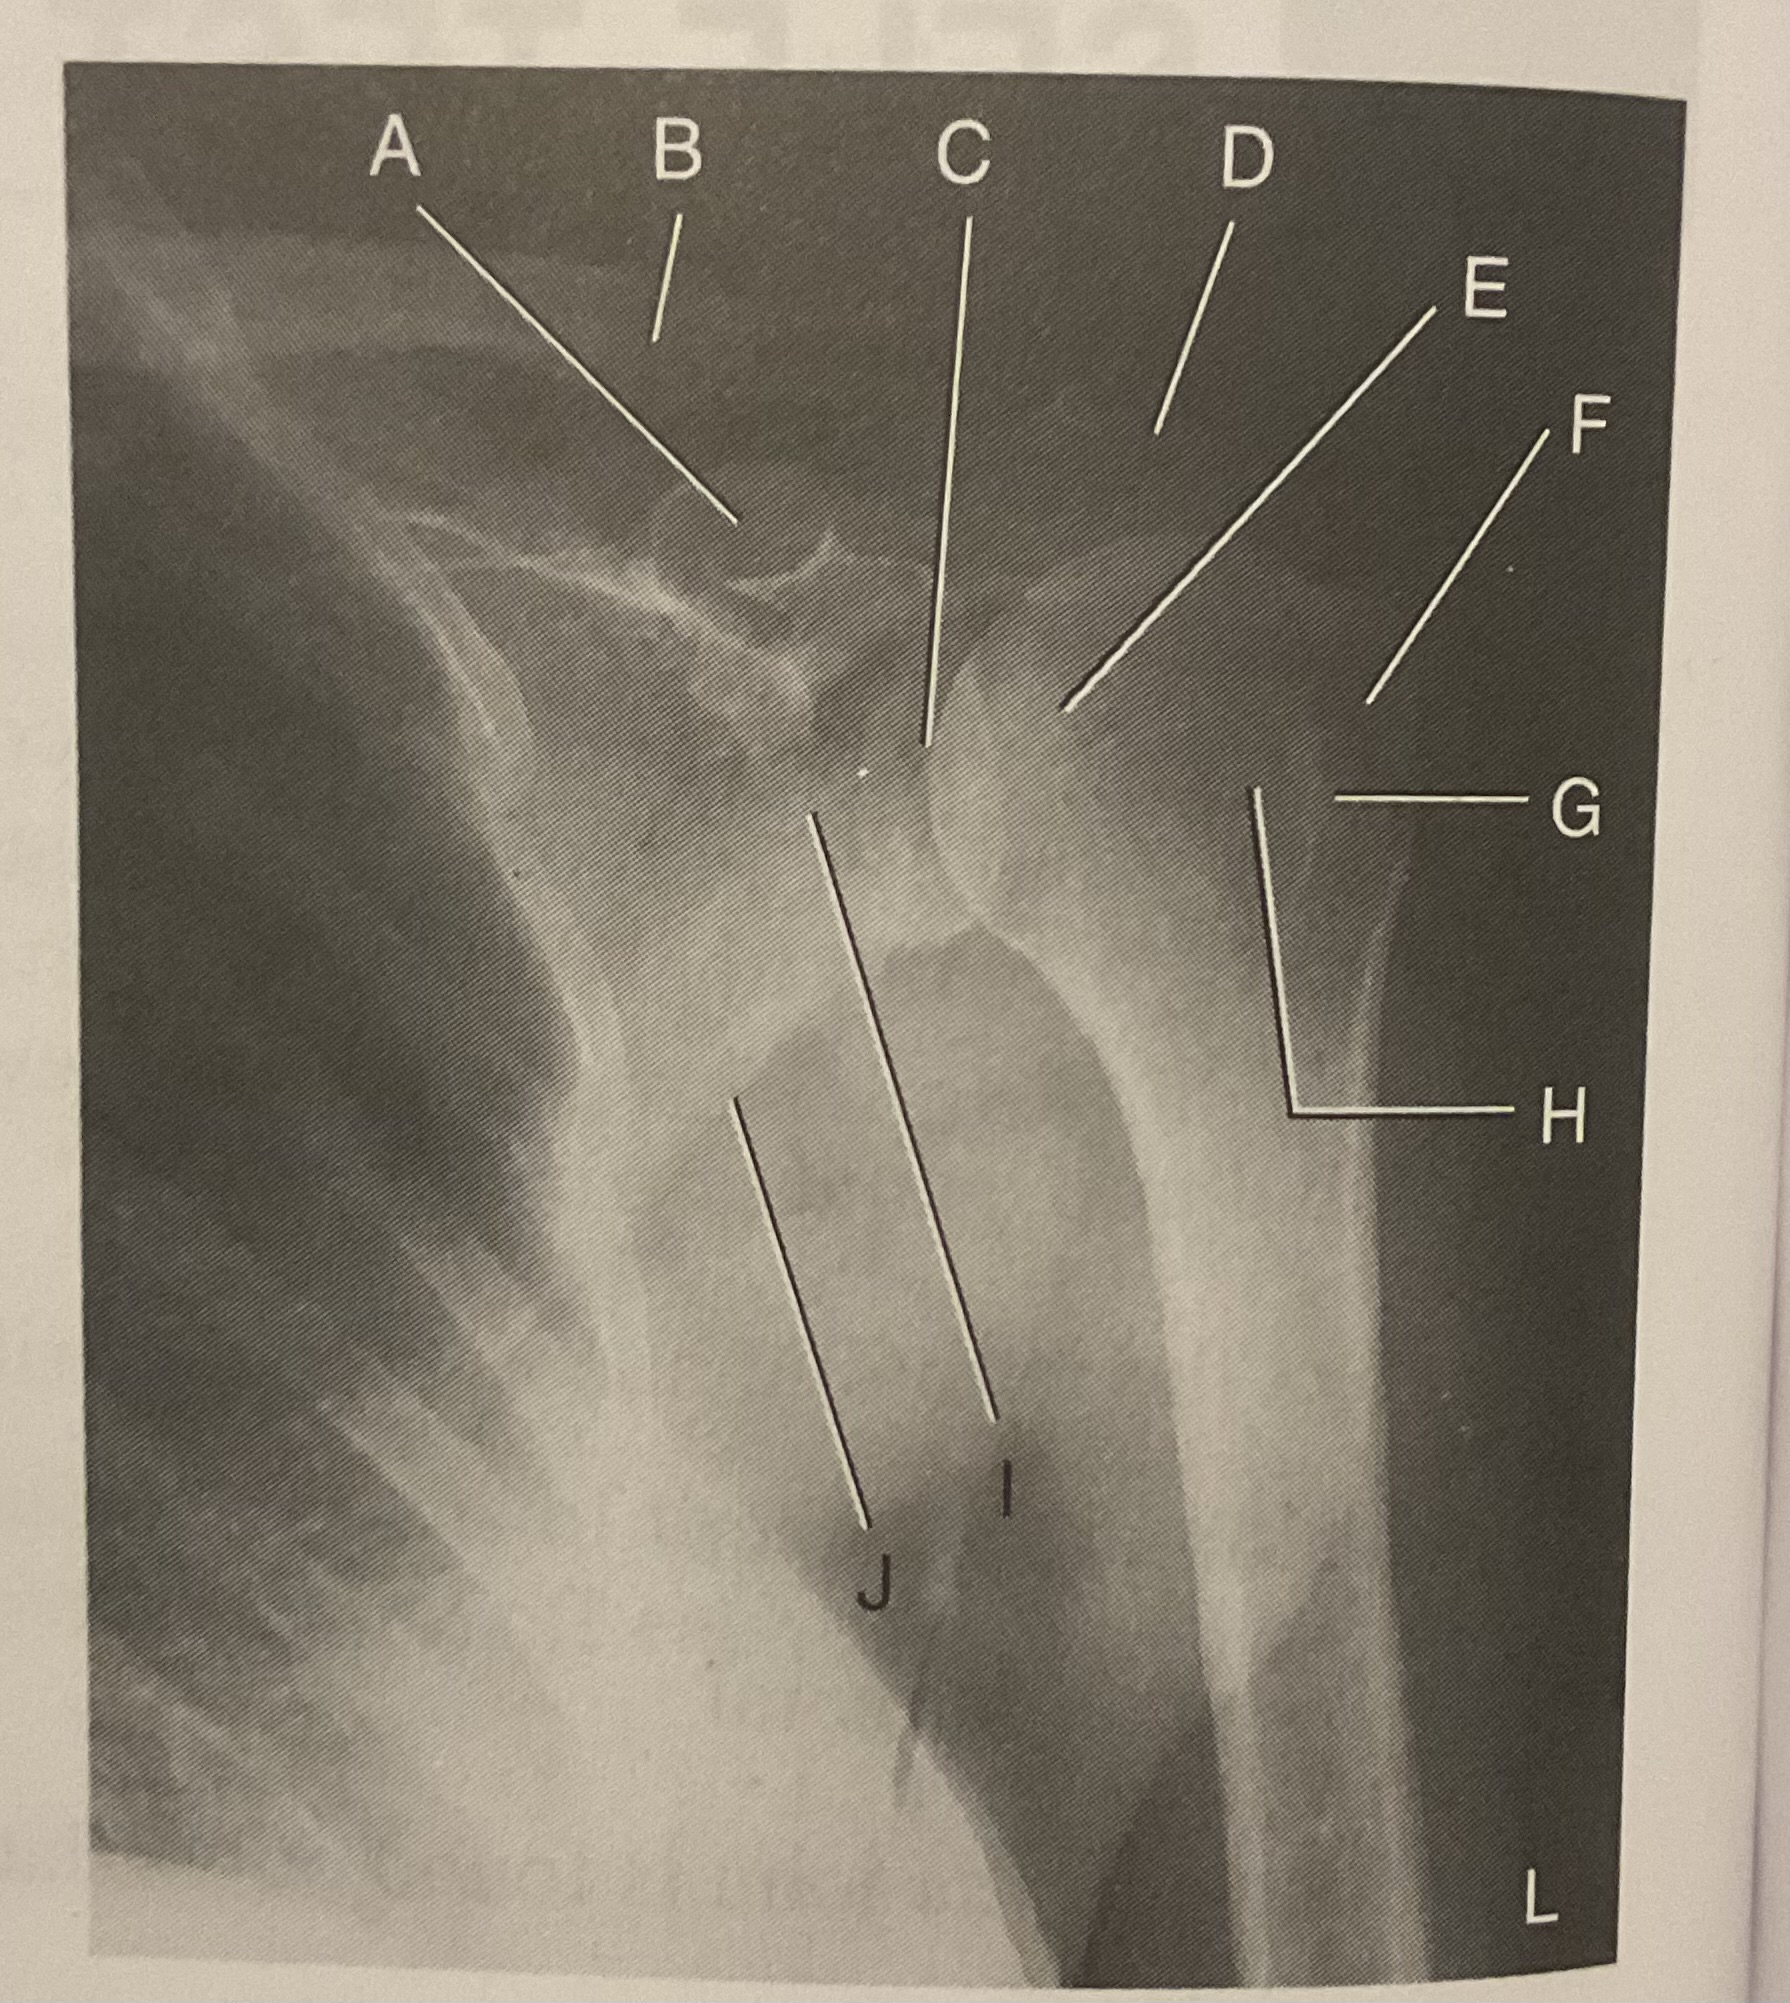

A?

Coracoid process

B?

Clavicle

C?

Scapulohumeral joint

D?

Acromion of scapula

E?

Head of humerus

F?

Greater tubercle

G?

Intertubercular sulcus

H?

Lesser tubercle

I?

Neck of scapula

J?

Lateral (axillary) border of scapula

What AP projection does this image represent?

External